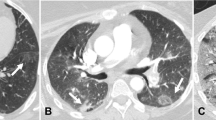

Detailed images of TIB and VEP are available in Fig. 1.

CT scans showing vascular enlargement pattern (VEP) and vascular tree-in-bud (TIB) in two patients with COVID-19 pneumonia. Notes: A—Bilateral peripheral areas of ground-glass opacification and crazy paving in the upper lobes. Dilated segmental and subsegmental vessels (VEP—arrowheads) are visible inside these areas. B—Targeted image shows striking dilatation of peripheral subpleural vessel in upper left lobe with a branching aspect resembling a budding tree (arrow). Please note that vascular TIB is visible only within the area of ground-glass-opacity in this picture